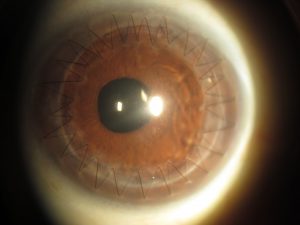

Gözümüzün en ön parçasını oluşturan ve net görmemizde önemli katkı sağlayan kornea dokusunun 7-9 mm’lik bir kısmının çıkartılarak yerine aynı çaptaki donör korneasının dikilmesi işlemine keratoplasti (Kornea nakli) denir.

KORNEA NAKLİ (KERATOPLASTİ) KİMLERE YAPILIR?

İleri keratokonus,

Travmatik santral kornea skarları,

Görmeyi engelleyen kornea distrofileri

Geçirilmiş enfeksiyonlara bağlı korneal lökomlar.

5-Keratoplasti (Kornea nakli) ne zaman gereklidir?

İleri evre keratokonus olgularında, görmenin çok azaldığı ve kornea opasitelerinin geliştiği olgular için gereklidir.